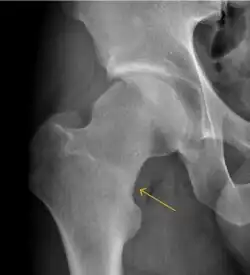

Plain radiography allows us to categorize the hip as normal or dysplastic or with impingement signs (pincer, cam, or a combination of both). Besides these, pathologic processes like osteoarthritis, inflammatory diseases, infection, or tumors can also be identified (Figure 1).[1]

Figure 1.

-

Radiography in normal hip -

X-ray in pincer impingement type of hip dysplasia -

X-ray of cam -

Hip in osteoarthritis -

Septic arthritis

- Osteoarthritis

In adults, one of the main indications for radiographs is the detection of osteoarthritic changes (Figure 1(e)). Nevertheless, radiographs usually detect advanced osteoarthritis that can be graded according to the Tönnis classifications. The grading system ranges from 0 to 3, where 0 shows no sign of osteoarthritis. Intermediate grade 1 shows mild sclerosis of the head and acetabulum, slight joint space narrowing, and marginal osteophyte lipping. Grade 2 presents with small cysts in the femoral head or acetabulum, moderate joint space narrowing, and moderate loss of sphericity of the femoral head. Grade 3 is the severest form of osteoarthritis, which manifests as severe narrowing of the joint space, large subchondral cyst with productive bone changes that may lead to deformity of the bone components of the joint, while secondary osteoarthritis due to calcium pyrophosphate deposition can be diagnosed when calcification of hyaline cartilage and fibrocartilage is detected.[1]

There are other pathological conditions that can affect the hip joint and radiographs help to make the appropriate diagnosis. Acute bacterial septic arthritis can be diagnosed by radiographs when a fast regional osteoporosis and destructive monoarticular process develops (Figure 1(f)). In case of tuberculous or brucella arthritis it is manifested as a slow progressive process, and diagnosis may be delayed.[1]